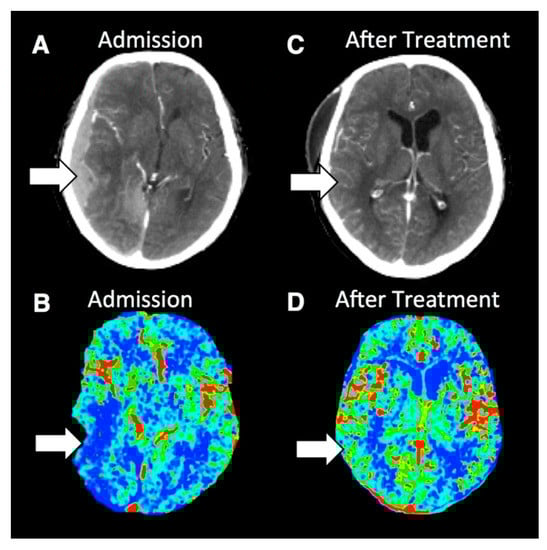

Figure 5.

Noncontrast and perfusion computed tomography (PCT) images from a patient with severe traumatic brain injury (TBI). (A) Noncontrast CT at admission revealed a small hemorrhagic contusion in the right frontal lobe (arrow). Admission PCT images demonstrates a large territory of decreased regional cerebral blood volume (rCBV) (B), increased mean transit time (MTT) (C) and decreased regional cerebral blood flow (rCBF) (D). Follow-up noncontrast CT at 24 h (E) demonstrates increased areas of hemorrhagic contusion in the right frontal lobe where the perfusion abnormality was seen. Follow-up noncontrast CT at 15-days (F) demonstrates evolving hemorrhagic contusion and encephalomalacia in the right frontal lobe, which corresponds to the same distribution that is seen on the perfusion-CT on admission. Reprinted with permission from [].

Figure 6.

Contrast-enhanced and PCT images from a patient with severe TBI. (A) Contrast-enhanced CT imaging at admission demonstrates a right-sided subdural hematoma causing mass effect on the underlying brain and midline shift. (B) rCBF PCT imaging at admission demonstrates decreased rCBF in the right temporal lobe. (C) Contrast-enhanced CT image after surgical evacuation of the hematoma demonstrates resolution of the right-sided subdural hematoma, mass effect and midline shift. (D) rCBF PCT imaging after surgical evacuation of the right-sided hematoma demonstrates normalization of the rCBF in the right temporal lobe. Reprinted with permission from [].

Figure 7.

Contrast-enhanced and PCT images of a case of TBI with intracranial hypertension. The contrast enhanced CT (A) demonstrated left-sided scalp hematoma. The rCBF (B) and rCBV (C) trended toward lower values especially in the occipital lobes. The MTT (D) demonstrated significantly higher values, reflecting altered cerebral autoregulation after TBI. Reprinted with permission from [].

Just as TBI is a heterogenous pathology, so too are the patterns of perfusion abnormalities seen in TBI. Multiple studies have documented perfusion defects seen in TBI patients in a variety of sites throughout the brain [,,,,,,]. Abnormal perfusion has been identified in the context of cerebral edema, extra-axial collections, and intracranial hypertension [,], see Figure 5, Figure 6 and Figure 7. One study has suggested that PCT may be able to distinguish whether an area of hypodensity on noncontrast CT is necrotic or viable, something that is not possible on noncontrast CT alone []. Still further, PCT provides insight into cerebral autoregulation, which can be used to help guide therapy [].